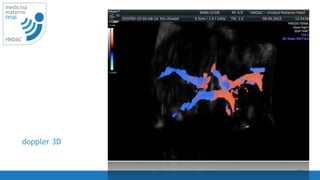

doppler 3D

20